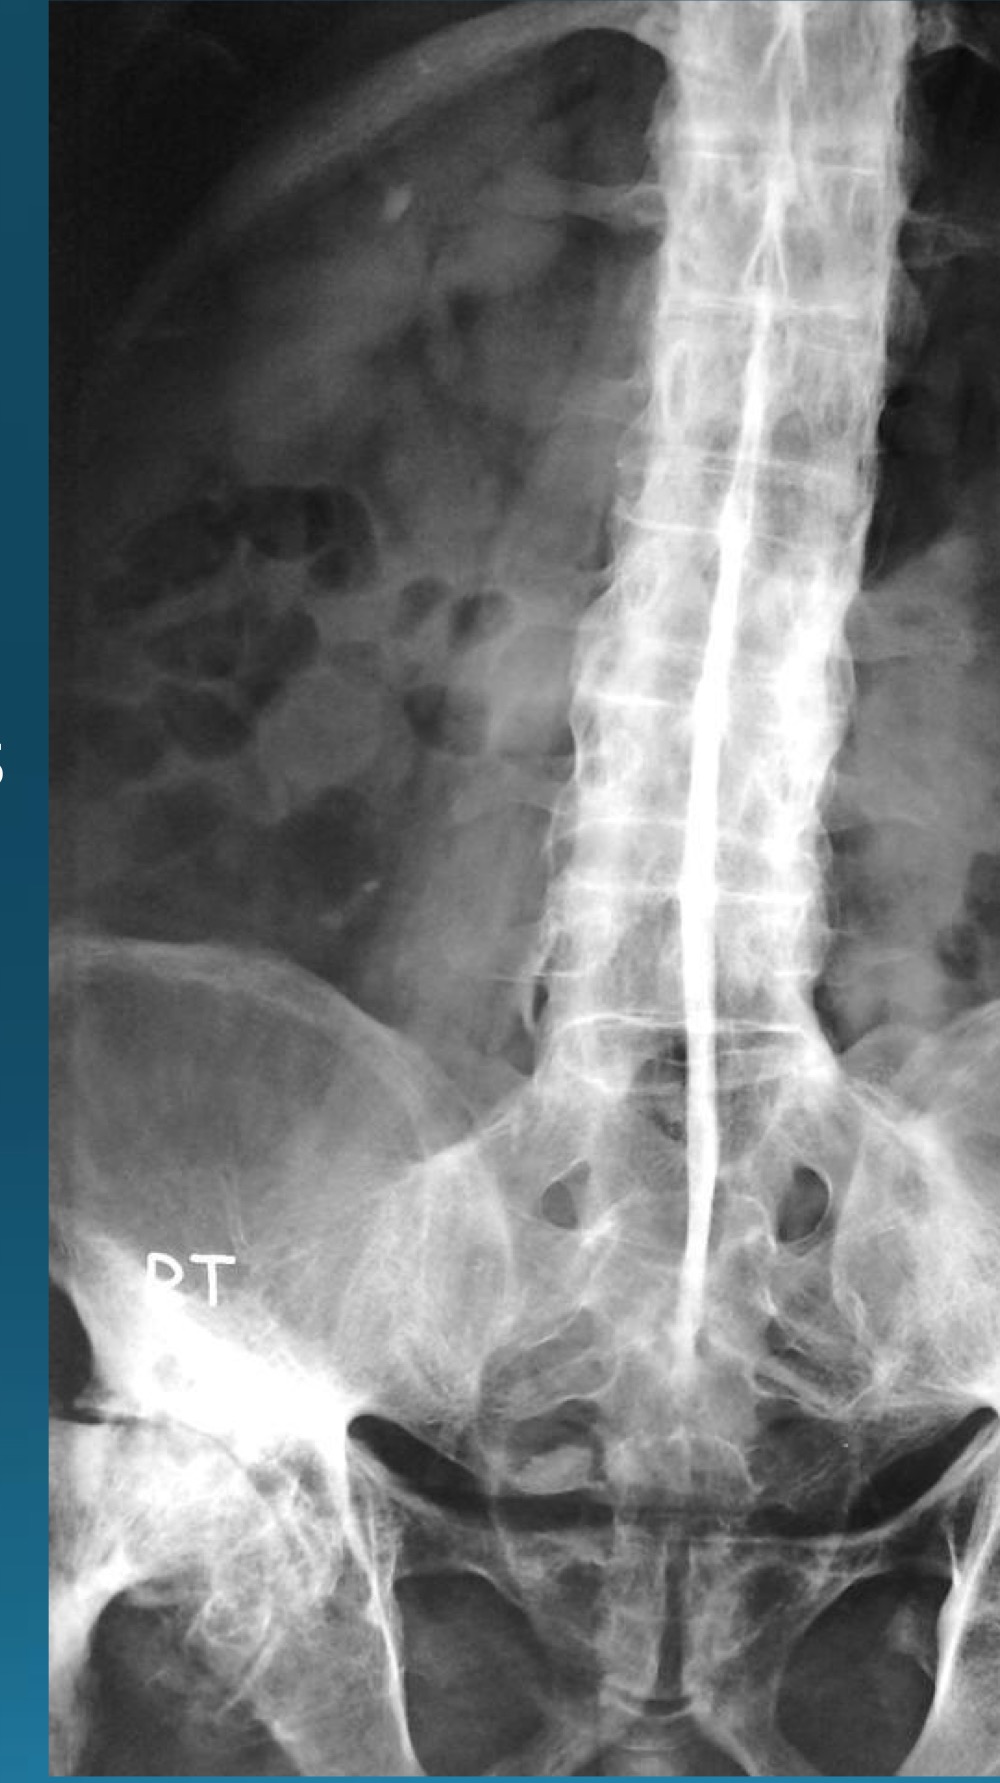

what do you call this sign? what diangosis is this apart of?

dagger sign

AS